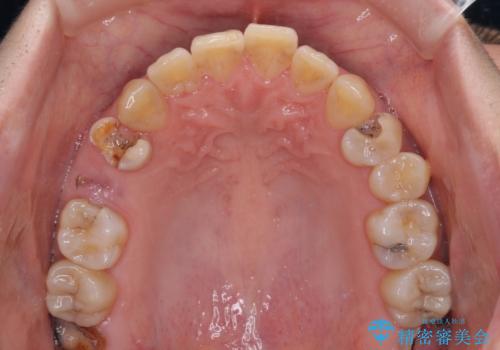

- 奥歯に問題が多くて困っているとのことで来院された患者様です。

開咬により奥歯のみが接触している状態で、前歯部にほとんど接触のない状態で、奥歯に非常に負担のかかる咬み合わせでした。

また、欠損や根管治療の必要な歯など、むし歯による問題も多く散見されました。

まずはむし歯の治療を行い、その後ワイヤー矯正にて咬み合わせを改善し、途中インプラント埋入を行い、矯正治療後に補綴治療を行うこととしました。